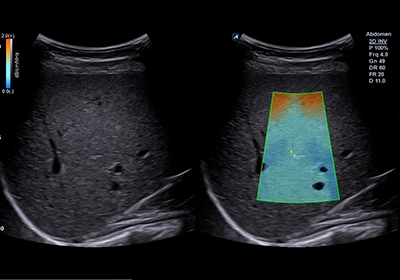

- 脂肪肝是個常見的疾病也是讓患者以及醫師會忽略的疾病。近幾年來醫學界發現脂肪肝若有發炎或者合併肝纖維化容易在中老年時期有心血管疾病、心肌梗塞、腦中風、腎臟衰竭、肝硬化併發症、以及其他器官的癌症的發生。在美國有1/3因脂肪肝併發癌症,同時也是美國肝臟移植的主要原因。美國國際醫學會以及歐洲醫學會的數據顯示ATI超音波技術對脂肪肝的分層診斷精確度已經超過昂貴的核磁共振以及電腦斷層。本院於2024年9月率先引進ATI超音波脂肪肝診斷技術讓患者不用再住院切片即能精確診斷脂肪肝的嚴重程度。讓患者可以積極的介入治療,避免中老年時期脂肪肝合併症的發生。